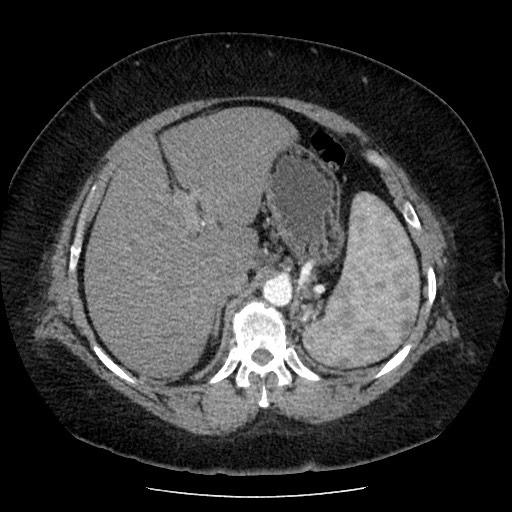

CT of the abdomen demonstrates a mass arising from the greater curvature of the body of the stomach. It is centrally ulcerated with locules of gas and contrast seen within it, but without evidence of perforation. It is a focal abnormality with thick heaped-up shoulders.

At the splenic hilum there appears to be an enlarged lymph node (this should be confirmed on thin slice and coronal reformats). No convincing evidence of metastatic disease.

The left kidney is atrophic and contains a number of what appear to be hyperdense cysts (which should be confirmed on ultrasound). The right kidney has a large simple cyst.

This patient went on to have a total gastrectomy after the stomach tumour was identified on gastroscopy.